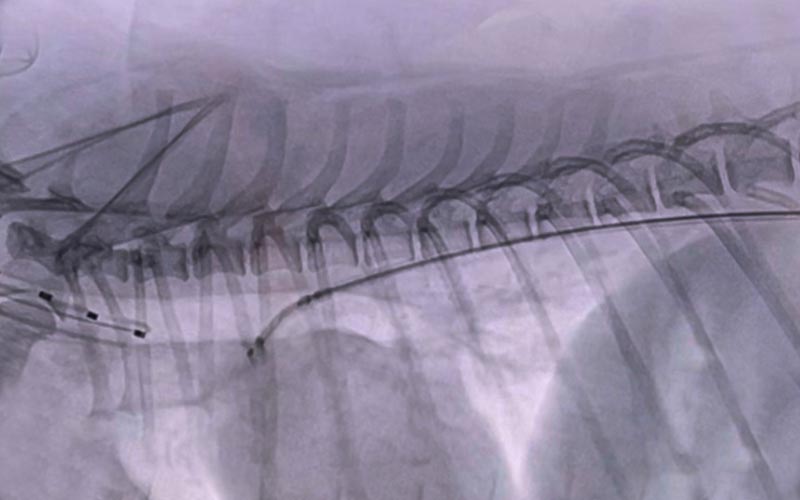

문맥전신단락증(Portosystemic Shunt)

션트 색전술 (혈관 내 폐쇄 장치 삽입)

• 개복 없이 혈관 내로 접근해 체내 부담을 최소화

• 간으로 가는 혈류를 회복시켜 신경·소화 증상 개선 기대

• 수술 후 회복이 빠르고 합병증 발생률을 낮출 수 있음